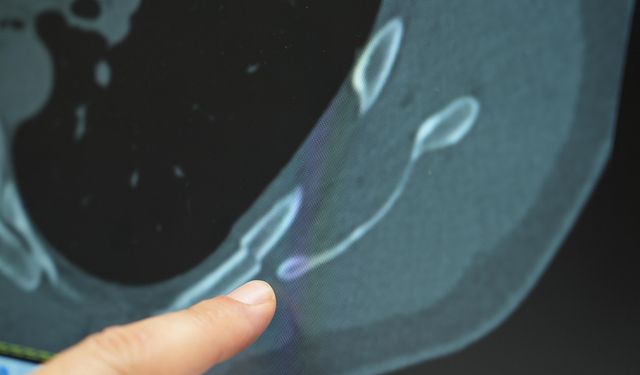

31 ülkede kolera salgını alarm veriyor!